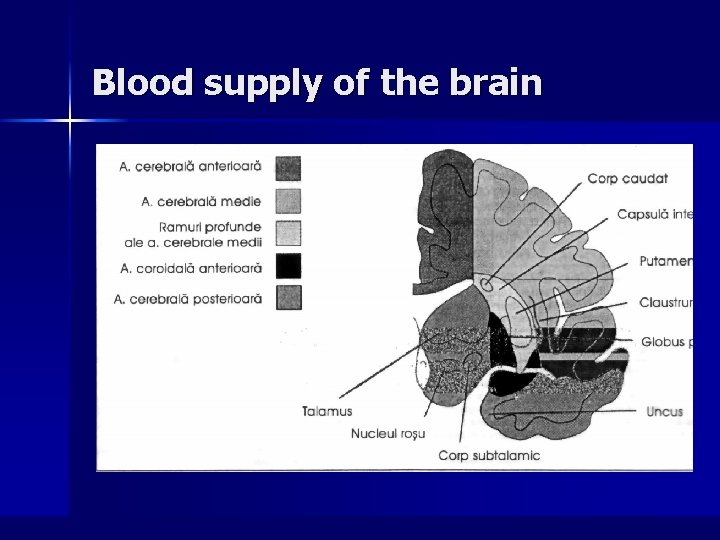

Blood supply of the brain

Cerebral Anatomy n n Vascular circulation: Anterior and Posterior Anterior circulation – Origin: carotid system – supplies 80% brain- optic nerve, retina, frontoparietal and anterotemporal lobes of brain n Posterior circulation: – – – supplies 20% of brain Derived from vertebral arteries Supplies brainstem, cerebellum, thalamus, auditory centers and visual cortex

Cerebral Arteries Areas 1 1. anterior cerebral 3 2 2. Middle cerebral 3. Penetrating branches of middle cerebral 54 5 4. anterior choroidal 5. Posterior cerebral